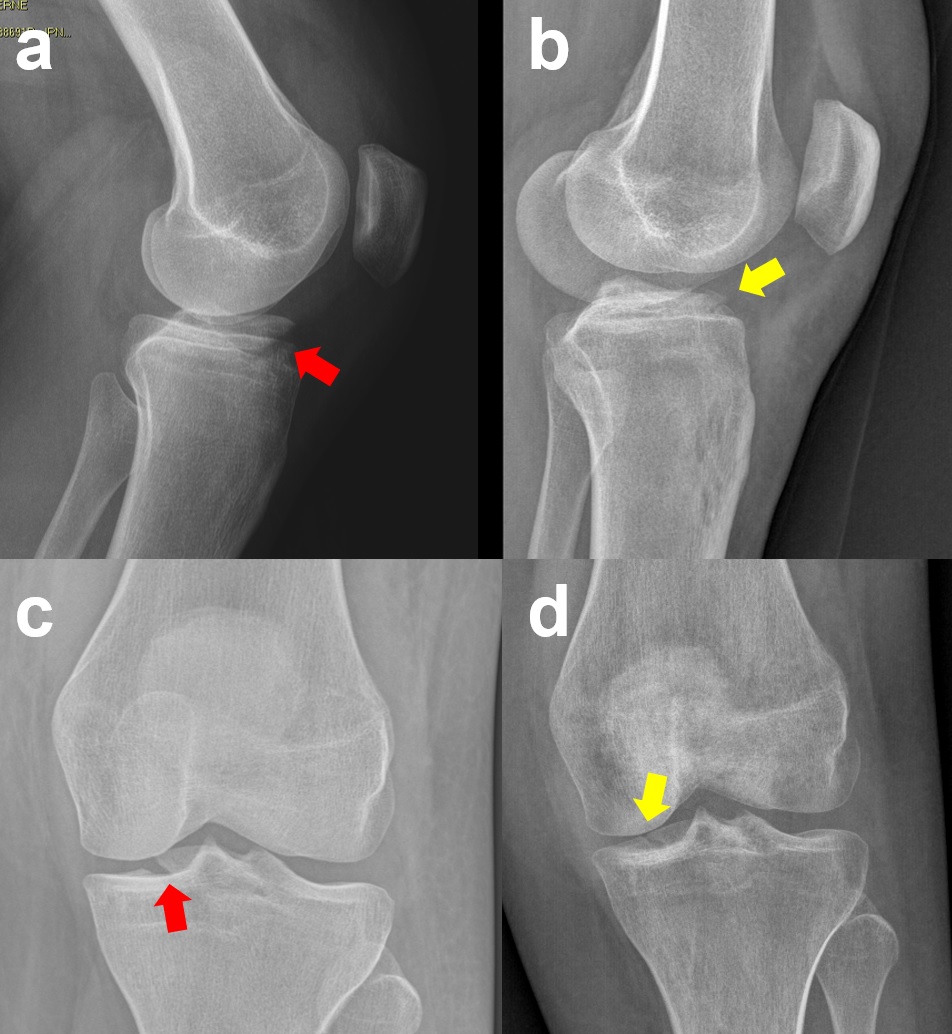

Case 3: A 24-year-old female tennis player sustained a left knee sprain while skiing. The initial X-ray was interpreted as negative, and the patient was initially treated conservatively in another institution. Due to the lack of extension, the patient underwent an MRI, which showed a Meyers and McKeevers Type III fracture (Figure 14a, c) with medial meniscus entrapment, medial meniscus posterior horn tear, and proximal medial collateral ligament (MCL) injury. After ARIF with absorbable sutures and medial meniscus repair performed 22 days after injury, good reduction and healing were obtained at the 8-week follow-up evaluation (Figure 14b, d). However, due to the late treatment, the patient developed arthrofibrosis, which was resolved after 6 months of intense rehabilitation. The patient returned to sport 7 months after injury.

Figure 14. A 24-year-old female with a Meyers and McKeevers Type III fracture (red arrow) in a sagittal MRI scan (a) and the healed and reduced fragment (yellow arrow) 8 weeks after surgery (b); coronal pre-operative (c) and post-operative (d) views of the same patient.